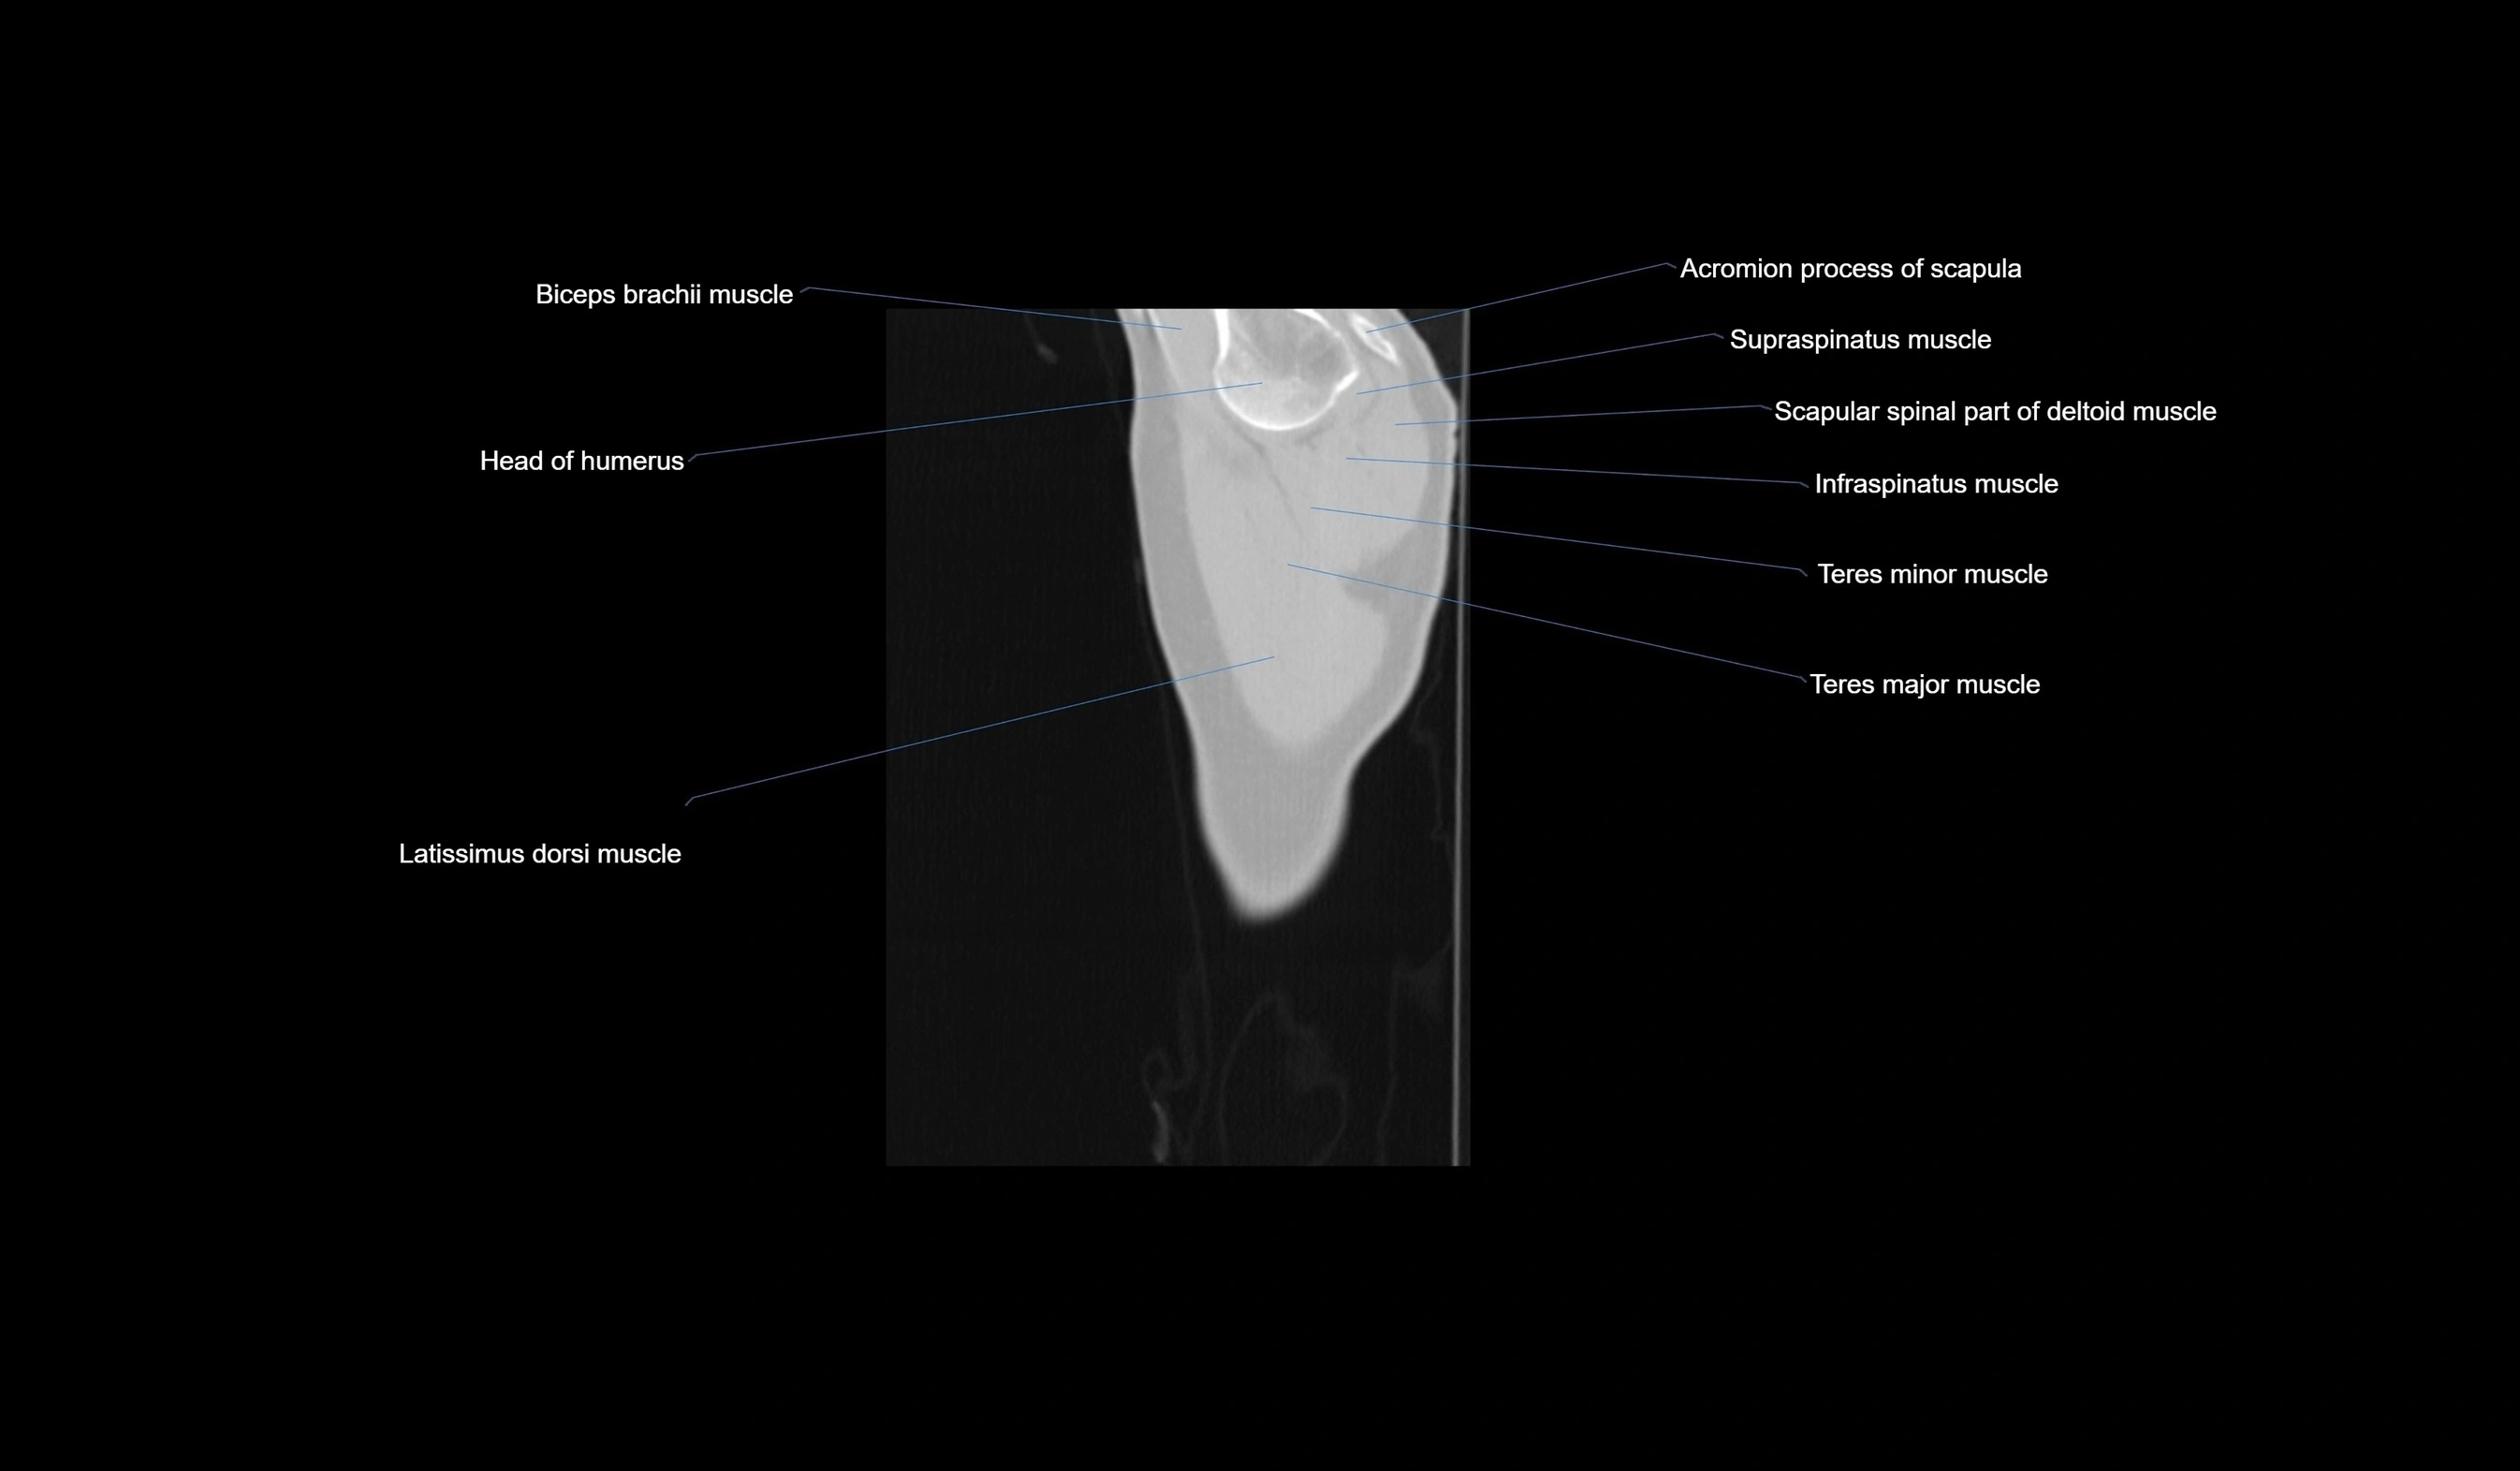

- Acromion process of scapula

- Anatomical neck of humerus

- Biceps brachii muscle

- Head of humerus

- Infraspinatus muscle

- Latissimus dorsi muscle

- Scapular spinal part of deltoid muscle

- Supraspinatus muscle

- Teres minor muscle

- Teres major muscle